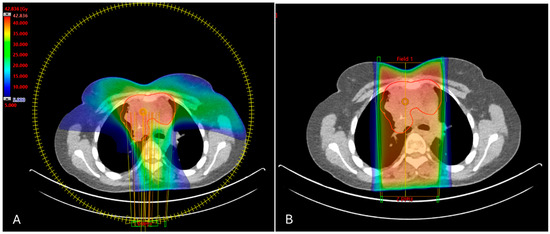

2. Methods

3.1. DVH Metrics